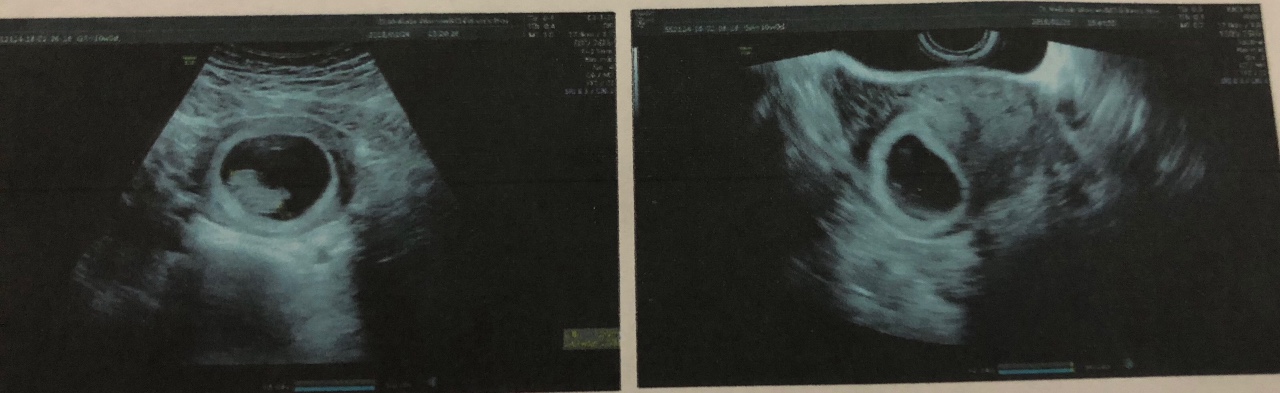

- УЗИ, во время которого не прослушивается биение сердца плода, наблюдается анэмбриония;

УЗИ на ранних сроках является наиболее достоверным методом определения патологии, который позволяет вовремя обнаружить: несоответствие размеров матки текущим срокам, отсутствие сердечного ритма и дыхания, остановку роста эмбриона, неправильное его положение и деформацию контуров вокруг тела плода, что может свидетельствовать о процессе разложения.

Показатели УЗИ

- Сердцебиение эмбриона не определяется. В норме на ультразвуковом исследовании оно заметно, начиная с 5 недели беременности.

- Плодное яйцо не имеет диаметра таких размеров, которые предполагает срок беременности.

- Величина эмбриона, находящегося в плодном яйце, не соответствует сроку беременности.

- Если срок до 4 недель, то признаком гибели плодного яйца является деформация.

- Эмбрион не визуализируется на сроке 6 – 7 недель.

Диагностика с помощью УЗИ

Признаки замершей беременности, например, на 8 или 10 неделе отчетливо определяются при первом проведении процедуры ультразвукового исследования. Но если срок еще мал, и не превышает 5 недель, то даже аппаратная диагностика способна сделать ошибку: не визуализировать эмбрион или не заметить его сердцебиение.

Самым точным способом определения замершей беременности и на ранних сроках, и на поздних, является УЗИ, в ходе которого специалист будет проверять:

- Несоответствие размера матки сроку беременности.

- Отсутствие сердцебиения и дыхательных движений.

- Неправильное положение, деформация и контур вокруг тела плода на поздних сроках, свидетельствующий о разложении тканей.

- Отсутствие визуализации и роста эмбриона на ранних сроках беременности. Очень редко, но бывает и так, что плодное яйцо еще какое-то время растет, а эмбрион в нем не формируется или остановился в развитии.